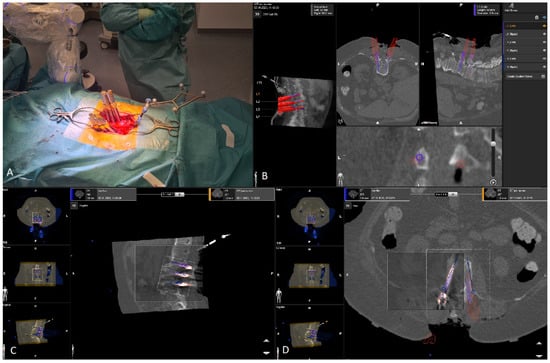

The kinematic unit of the Cirq® Robotic Alignment Module with the previously calibrated tracking array is positioned over the projection of the screw entry point. The instruments are tracked in real time, and their position is constantly reported back so that the surgeon can observe the movements of the robotic arm and all instruments on a separate monitor. The surgeon is located on the side of the robotic arm, i.e., on the left side of the patient. After positioning the robotic arm over the projection of the trajectory entry point, the robotic arm automatically aligns itself according to preplanned trajectory of the relevant screw. In percutaneous cases, a previously calibrated and registered trocar can be used to open the soft tissue for screw implantation, followed by the attachment of an instrument holder for the drill guide. A drill guide is then inserted through the tracking array with the instrument holder and positioned at the entry point, and attachable snap-on depth control for drilling is then attached. The tracking array is then locked, and drilling begins. In this step, it is crucial that the surgeon additionally stabilizes the instrument holder with sufficient pressure on the entry point to prevent skiving. A K-wire is implanted, and the robotic arm is removed. This workflow is repeated for all trajectories. All K-wires are secured to the cover with clamps to keep them in place. (Figure 10, Figure 11, Figure 12, Figure 13 and Figure 14) [4].

A 76-year-old patient with instability of the lumbar spine and a facet joint cyst at L3/4, following previous decompression at L2/3 on the right and L4/5 on the left, underwent RG PS implantation at L2–L5 with cage implantation (Figure 20).

A 78-year-old patient with a pathological fracture of Th10 due to breast cancer metastasis underwent multi-stage surgery: RG PS placement at Th8/9-L1/2, followed by implantation of an expandable vertebral body cage via a left transthoracic approach. All screws were GRS A (Figure 21).

An 81-year-old patient with spondylodiscitis, intraspinal empyema at L2-S1, and an L4 fracture underwent decompression for empyema evacuation and RG PS placement at L2-S1, followed by cage implantation (Figure 22, Figure 23 and Figure 24).

3.10.4. Screw Revision Case

A 63-year-old female patient with Th9 metastasis of renal cell carcinoma underwent Th7/8-10/11 RG stabilization with decompression of the spinal canal and partial resection of the tumor. The reference array was placed proximally to the surgical field and fixed to the spinous process of Th7. K-wires were inserted in a proximal-to-distal sequence, and screws were placed in a distal-to-proximal sequence. The distal screws (Th10/11) were GRS A screws, while the last screw (left Th7 screw) was a GRS E screw due to possible unintended movement of the reference array, which led to major navigation inaccuracy and further screw skiving. Fortunately, no major vessels or pulmonary injuries occurred. The screw was removed, and a new screw was inserted, this time a GRS A screw. (Figure 25).

3.10.5. Robot Abandonment Case

A 77-year-old adipose patient with Bechterew’s disease suffered a C6 fracture with instability. He underwent a multi-stage operation, in which the ventral fracture was reduced, and an expandable vertebral body cage with plate was implanted, followed by dorsal stabilization with lateral mass screws at C3/4/5/6 and PSs at C7/Th1/2/3. The reference array was placed on the spinous process of Th5. The cervical screws were placed using the navigated drill guide. Thoracic PSs were planned for the RG surgery. The robotic arm was attached to the left side of the operating table. In the case of the Th1 PS on the right side, the trajectory angle and the soft tissue of the obese patient did not allow correct positioning of the kinematic unit of the robotic arm, so this screw was implanted using the navigated drill guide (Figure 26).